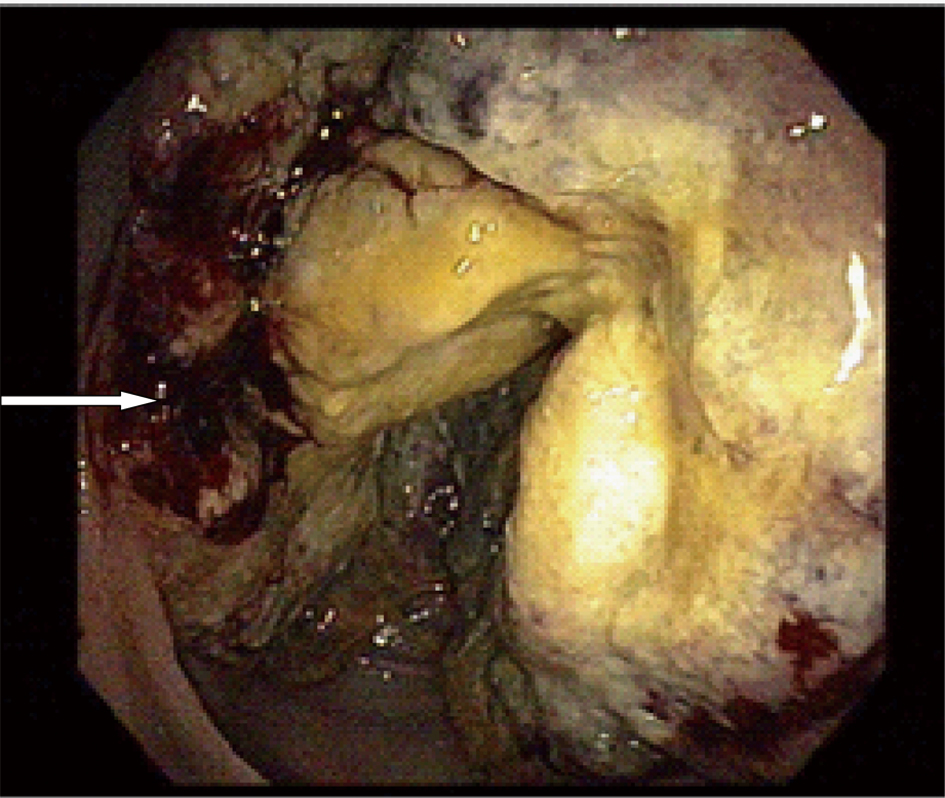

A 59-year-old male with a past medical history of hepatitis C and hypertension presented complaining of worsening abdominal pain associated with bright red blood per rectum for the past month. The pain was 7/10 in intensity, constant, non-radiating, with no alleviating or aggravating factors. He admits having 2 - 3 episodes of bloody stools per week. He also reported a 20 pounds weight loss in the last 6 months. Review of systems was otherwise negative. Social history was significant for a 15 pack year history. He denied family history gastrointestinal malignancies. Vitals on admission were within normal limits. Physical exam was significant for right upper quadrant tenderness without guarding, rebound, or organomegaly. Rectal exam revealed no blood or masses. Laboratory results showed iron deficiency anemia with hemoglobin of 9.6 K/mm3. Liver related tests and coagulation profile were within normal limits. Esophagogastroduodenoscopy revealed a 4mm duodenal polyp (Fig. 1). Colonoscopy was terminated early secondary to a large circumferential obstructing mass (Fig. 2) found in the descending colon. Immunohistochemistry of the duodenal biopsy was positive for synaptophysin and chromogranin-A (Fig. 3); consistent with the diagnosis of stage I carcinoid tumor. Biopsy results of the colonic mass showed a stage I well-differentiated adenocarcinoma (Fig. 4). The patient underwent a left colectomy and partial duodenectomy. He remains in remission after 2 year of close follow up.

![]() Click for large image | Figure 2. A large circumferential obstructing mass located 40 cm away from the anal verge with areas of hemorrhages (arrow). |